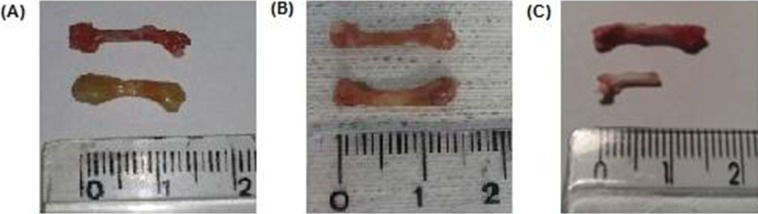

After 30 and 60 days, the inflammatory tissue reaction around the bone continued to occur, although less hyperemia was observed. Bone edema disappeared and was replaced by progressive brittleness and resorption. By 60 days, bone resorption and fragmentation were conspicuous, and in certain animals, as little as 50% of the original femur could be recovered from the subcutaneous pouch. Bone marrow changes suggestive of necrosis were also noted at 30 days and were more remarkable after 60 days (Figures 2 and 4).

Pictures of control (upper image) and grafted femur (lower image) at different times. A: 15 days, B: 30 days, C: 60 days. It is perceived that, after 15 days, the implant is swollen and enlarged. By 30 days, the edema had disappeared and was replaced by bone dryness and brittleness. However, the structural integrity was mostly maintained. At the last follow-up (60 days), severe bone resorption and fragmentation in some cases permitted the recovery of as little as 50% of the syngeneic bone only. However, in most animals, bone destruction was not as advanced as in this picture.